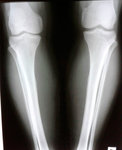

Дата операции 05.08.2017г.

Дата снятия аппаратов 27.11.2017г.

Срок лечения 110 дней.

IMG-20170804-WA0064.jpg

IMG-20170804-WA0062.jpg